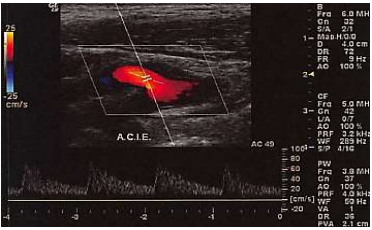

Assinale a alternativa que apresenta a melhor descrição do formato de onda mostrado na imagem abaixo.

Padrão monofásico com diástole normal em leito arterial de baixa resistência

Padrão bifásico com diástole normal em leito arterial de baixa resistência

Padrão trifásico com diástole normal em leito arterial de baixa resistência

Padrão bifásico com diástole normal em leito arterial de alta resistência

Padrão monofásico com diástole normal em leito arterial de alta resistência